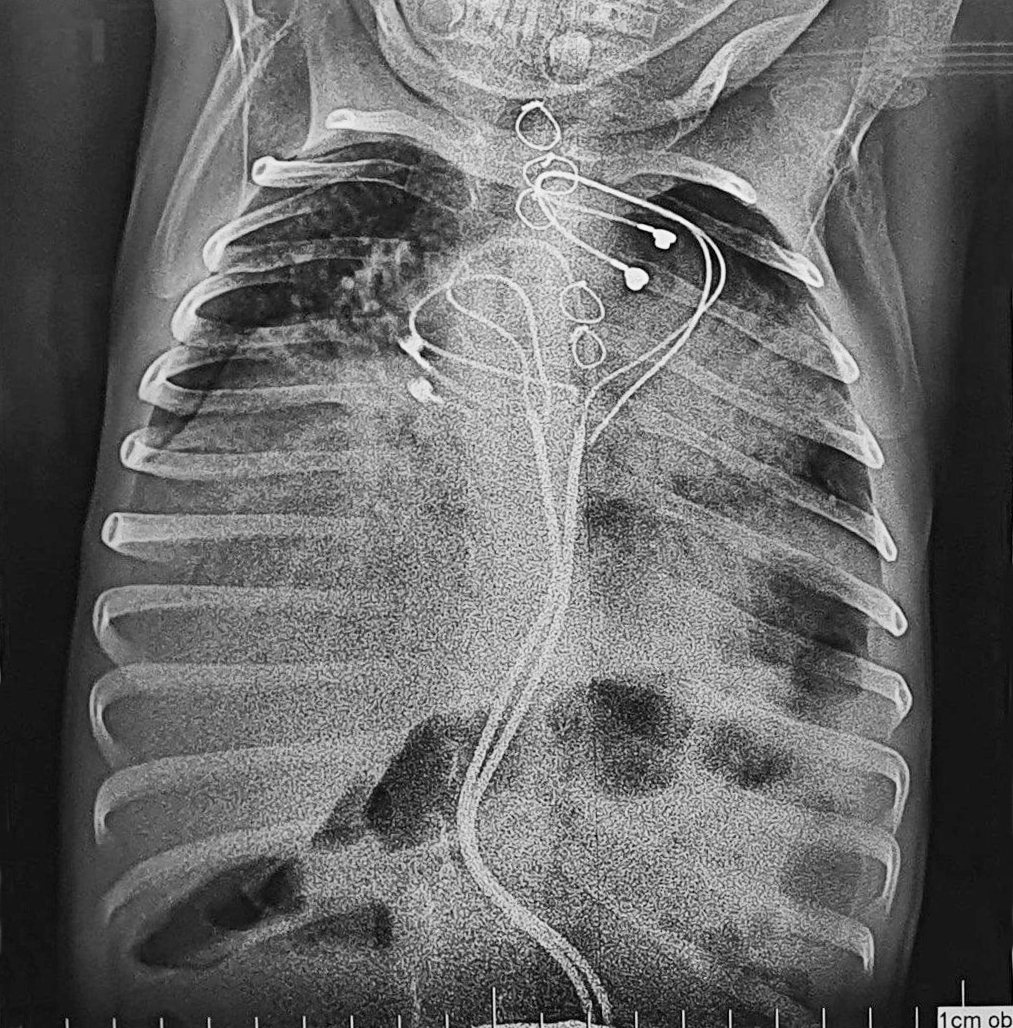

Прежде чем извлечь кардиостимулятор, предстояло найти ему альтернативу в поддержании работы сердца. Установка нового устройства стандартным образом - на противоположной стороне брюшной полости - была слишком рискованной из-за воспалительного процесса брюшной стенки, поэтому кардиохирурги Тимур Сагитович Хапаев и Сергей Михайлович Иванцов приняли решение имплантировать однокамерный кардиостимулятор в грудь - на реберно-диафрагмальную поверхность.

Вторым этапом приступили к открытой операции на брюшной полости. Хирурги Новосибирской областной больницы Владислав Николаевич Цыганок и Юрий Юрьевич Койнов очистили сигмовидную кишку от спаек, нашли место входа в нее кардиостимулятора и извлекли устройство обратно. Инфицированные электроды отсекли в месте входа в перикард. Дефект кишечной стенки закрыли, брюшную полость промыли. После курса антибактериальной терапии на 10-й день ребенок был выписан в удовлетворительном состоянии.